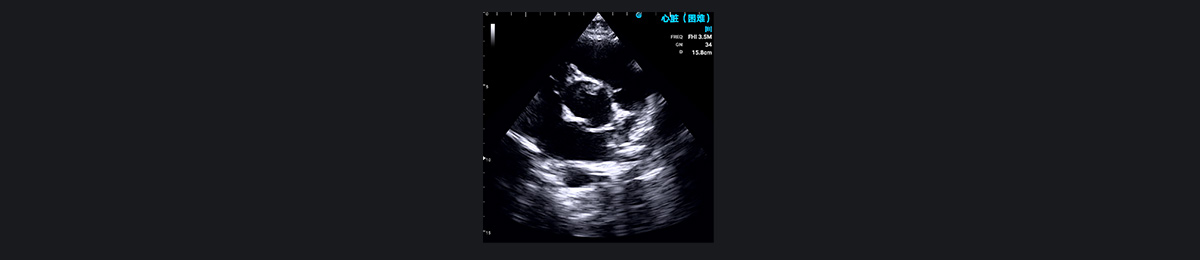

心包积液